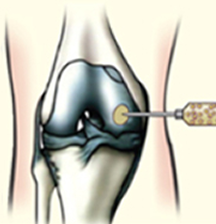

줄기세포 주사 이미지

골수액에서 분리 농축된 줄기세포 주사

자가골수줄기세포치료는 국소 마취 후 바늘을 이용해 자신의 골수에서 줄기세포를 채취하는 방식입니다. 원심분리기를 통해 줄기세포를 분리 농축하는데 이 때 줄기세포는 8~9억개의 재생세포로 분화됩니다. 손상된 무릎을 관절 내시경으로 보면서 주사로 줄기세포를 주입하면 시술은 종료됩니다.